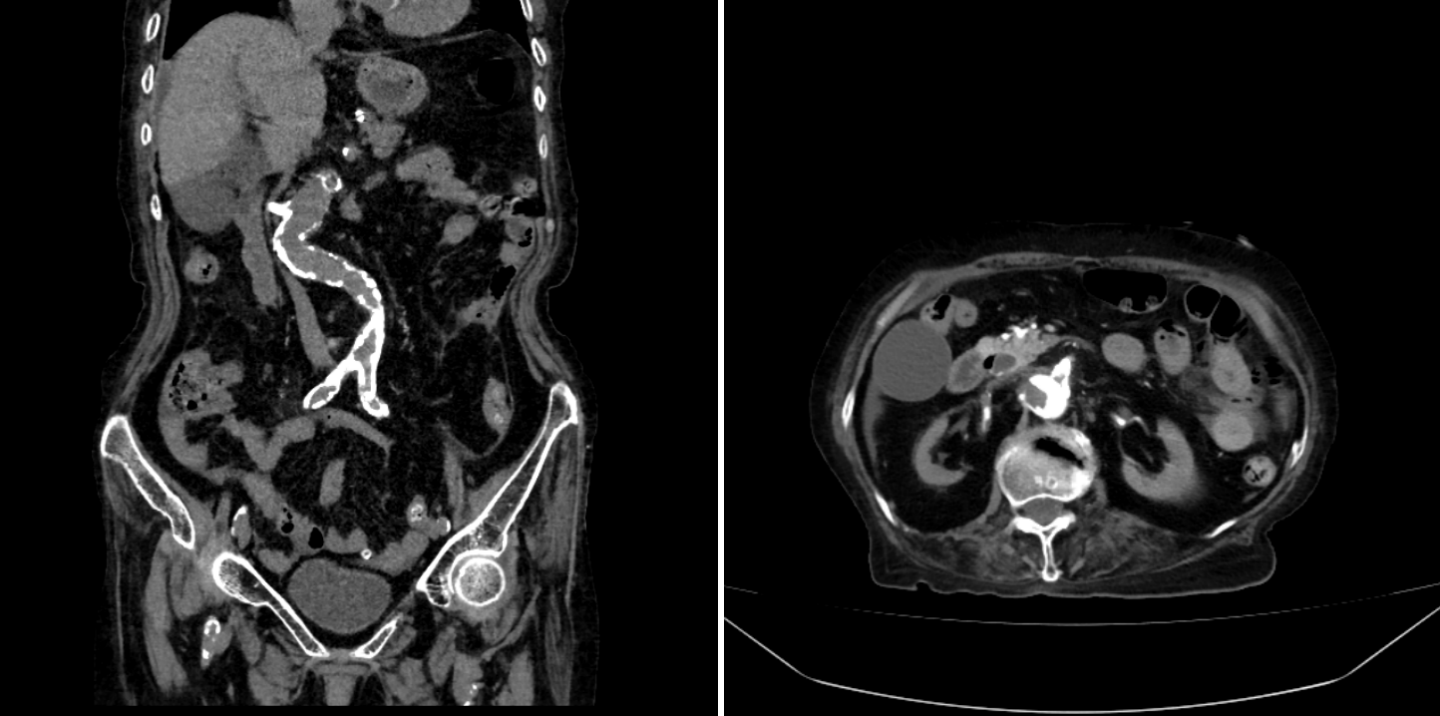

结果出来了,消化系统看起来并没有大问题,但有一条线索引起了医生们的注意:主动脉及分支动脉硬化非常严重,血管外科医生满新贺医生仔细看了看片子,还发现了更隐蔽的问题——陈阿姨的腹腔干动脉和肠系膜上动脉竟然严重狭窄,有的甚至闭塞了!

严重钙化的腹主动脉和肠系膜上动脉

“这是缺血性肠病!”满新贺一下就发现了病人的主要病因。满大夫才把这一发现告诉了陈阿姨和她的家人,最终家人同意进行血管介入开通手术。在杨永久主任指导下,手术进行得很顺利,满医生和郑医生用球囊把狭窄的血管撑开,还放进了支架,让供应小肠的血液重新顺畅地流动起来。